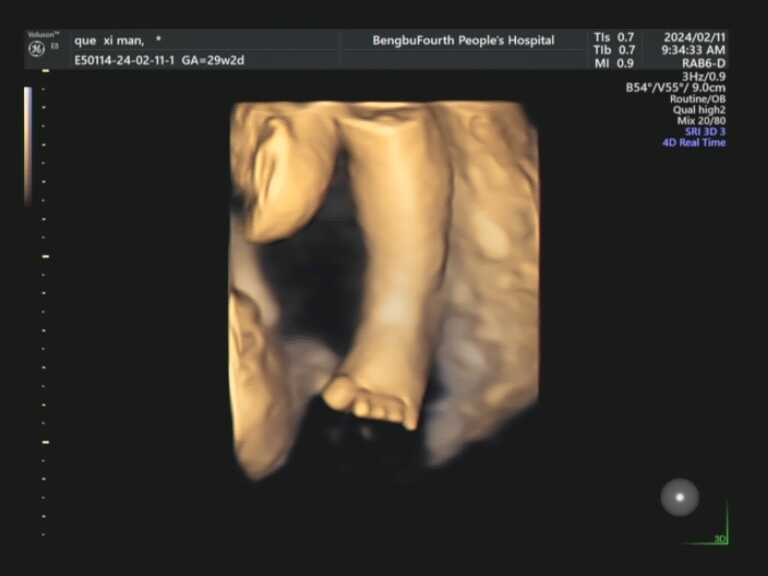

亲爱的准爸准妈,您是否无数次在梦中勾勒宝宝的模样?想象宝宝是像爸爸一样有着高挺的鼻梁,还是像妈妈一样爱笑?现在,您无需再等待十月之久。蚌埠市第四人民医院(市康复医院)高新院区超声科引进超高端美国GE-E8四维彩色超声诊断仪,将为您开启一场奇妙的生命探索之旅。这款被誉为“超声界网红”的设备,是胎儿排畸的顶端配置,搭载全球先进的电子曲面矩阵4D探头,能360°立体清晰展示胎儿各器官发育情况,精准捕捉每一个细节。

在这里,您将看到宝宝在子宫里打哈欠、吮手指、微笑、伸懒腰的可爱瞬间。在这里,您将获得宝宝人生中第一段动态“写真”和“照片”,成为您家庭最珍贵的回忆。